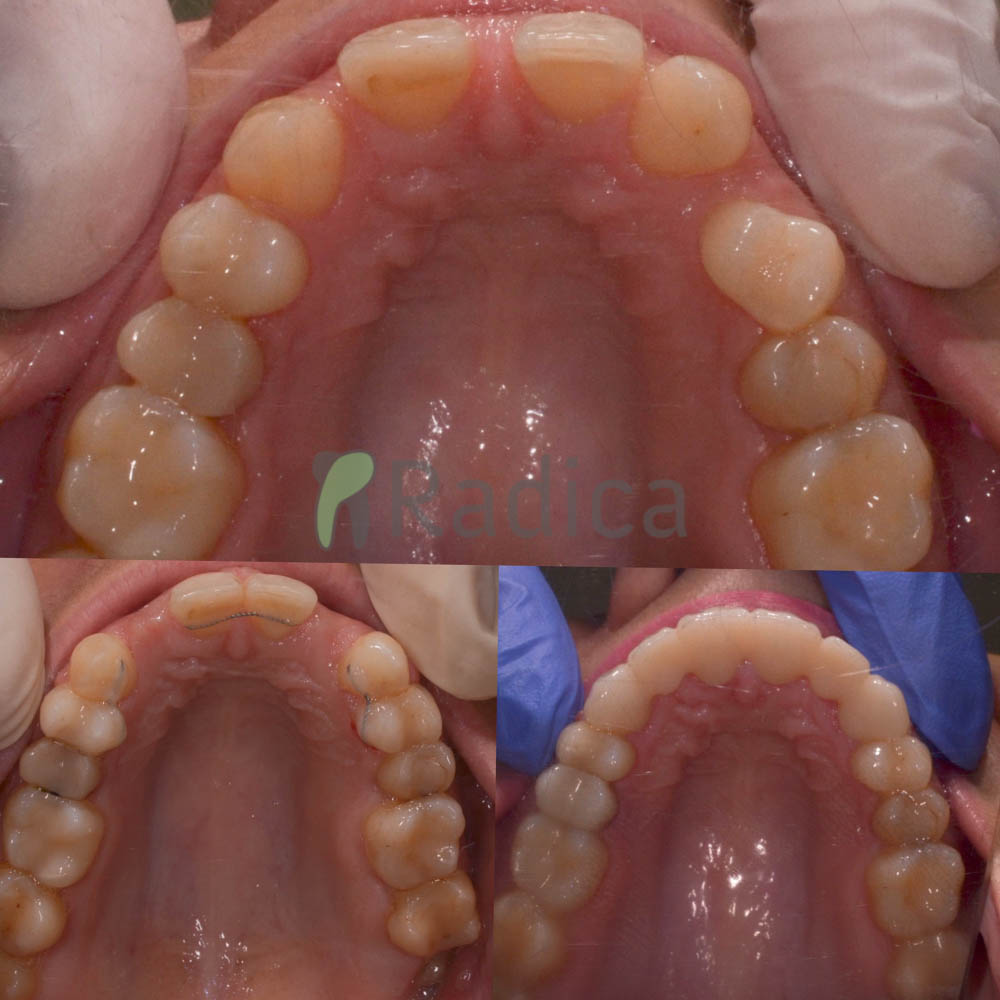

U galeriji slika su prikazani klinički slučajevi ovakvih odraslih pacijenta bilo da se radi samo o ortodontskoj terapiji ili predprotetskoj ortodonciji.